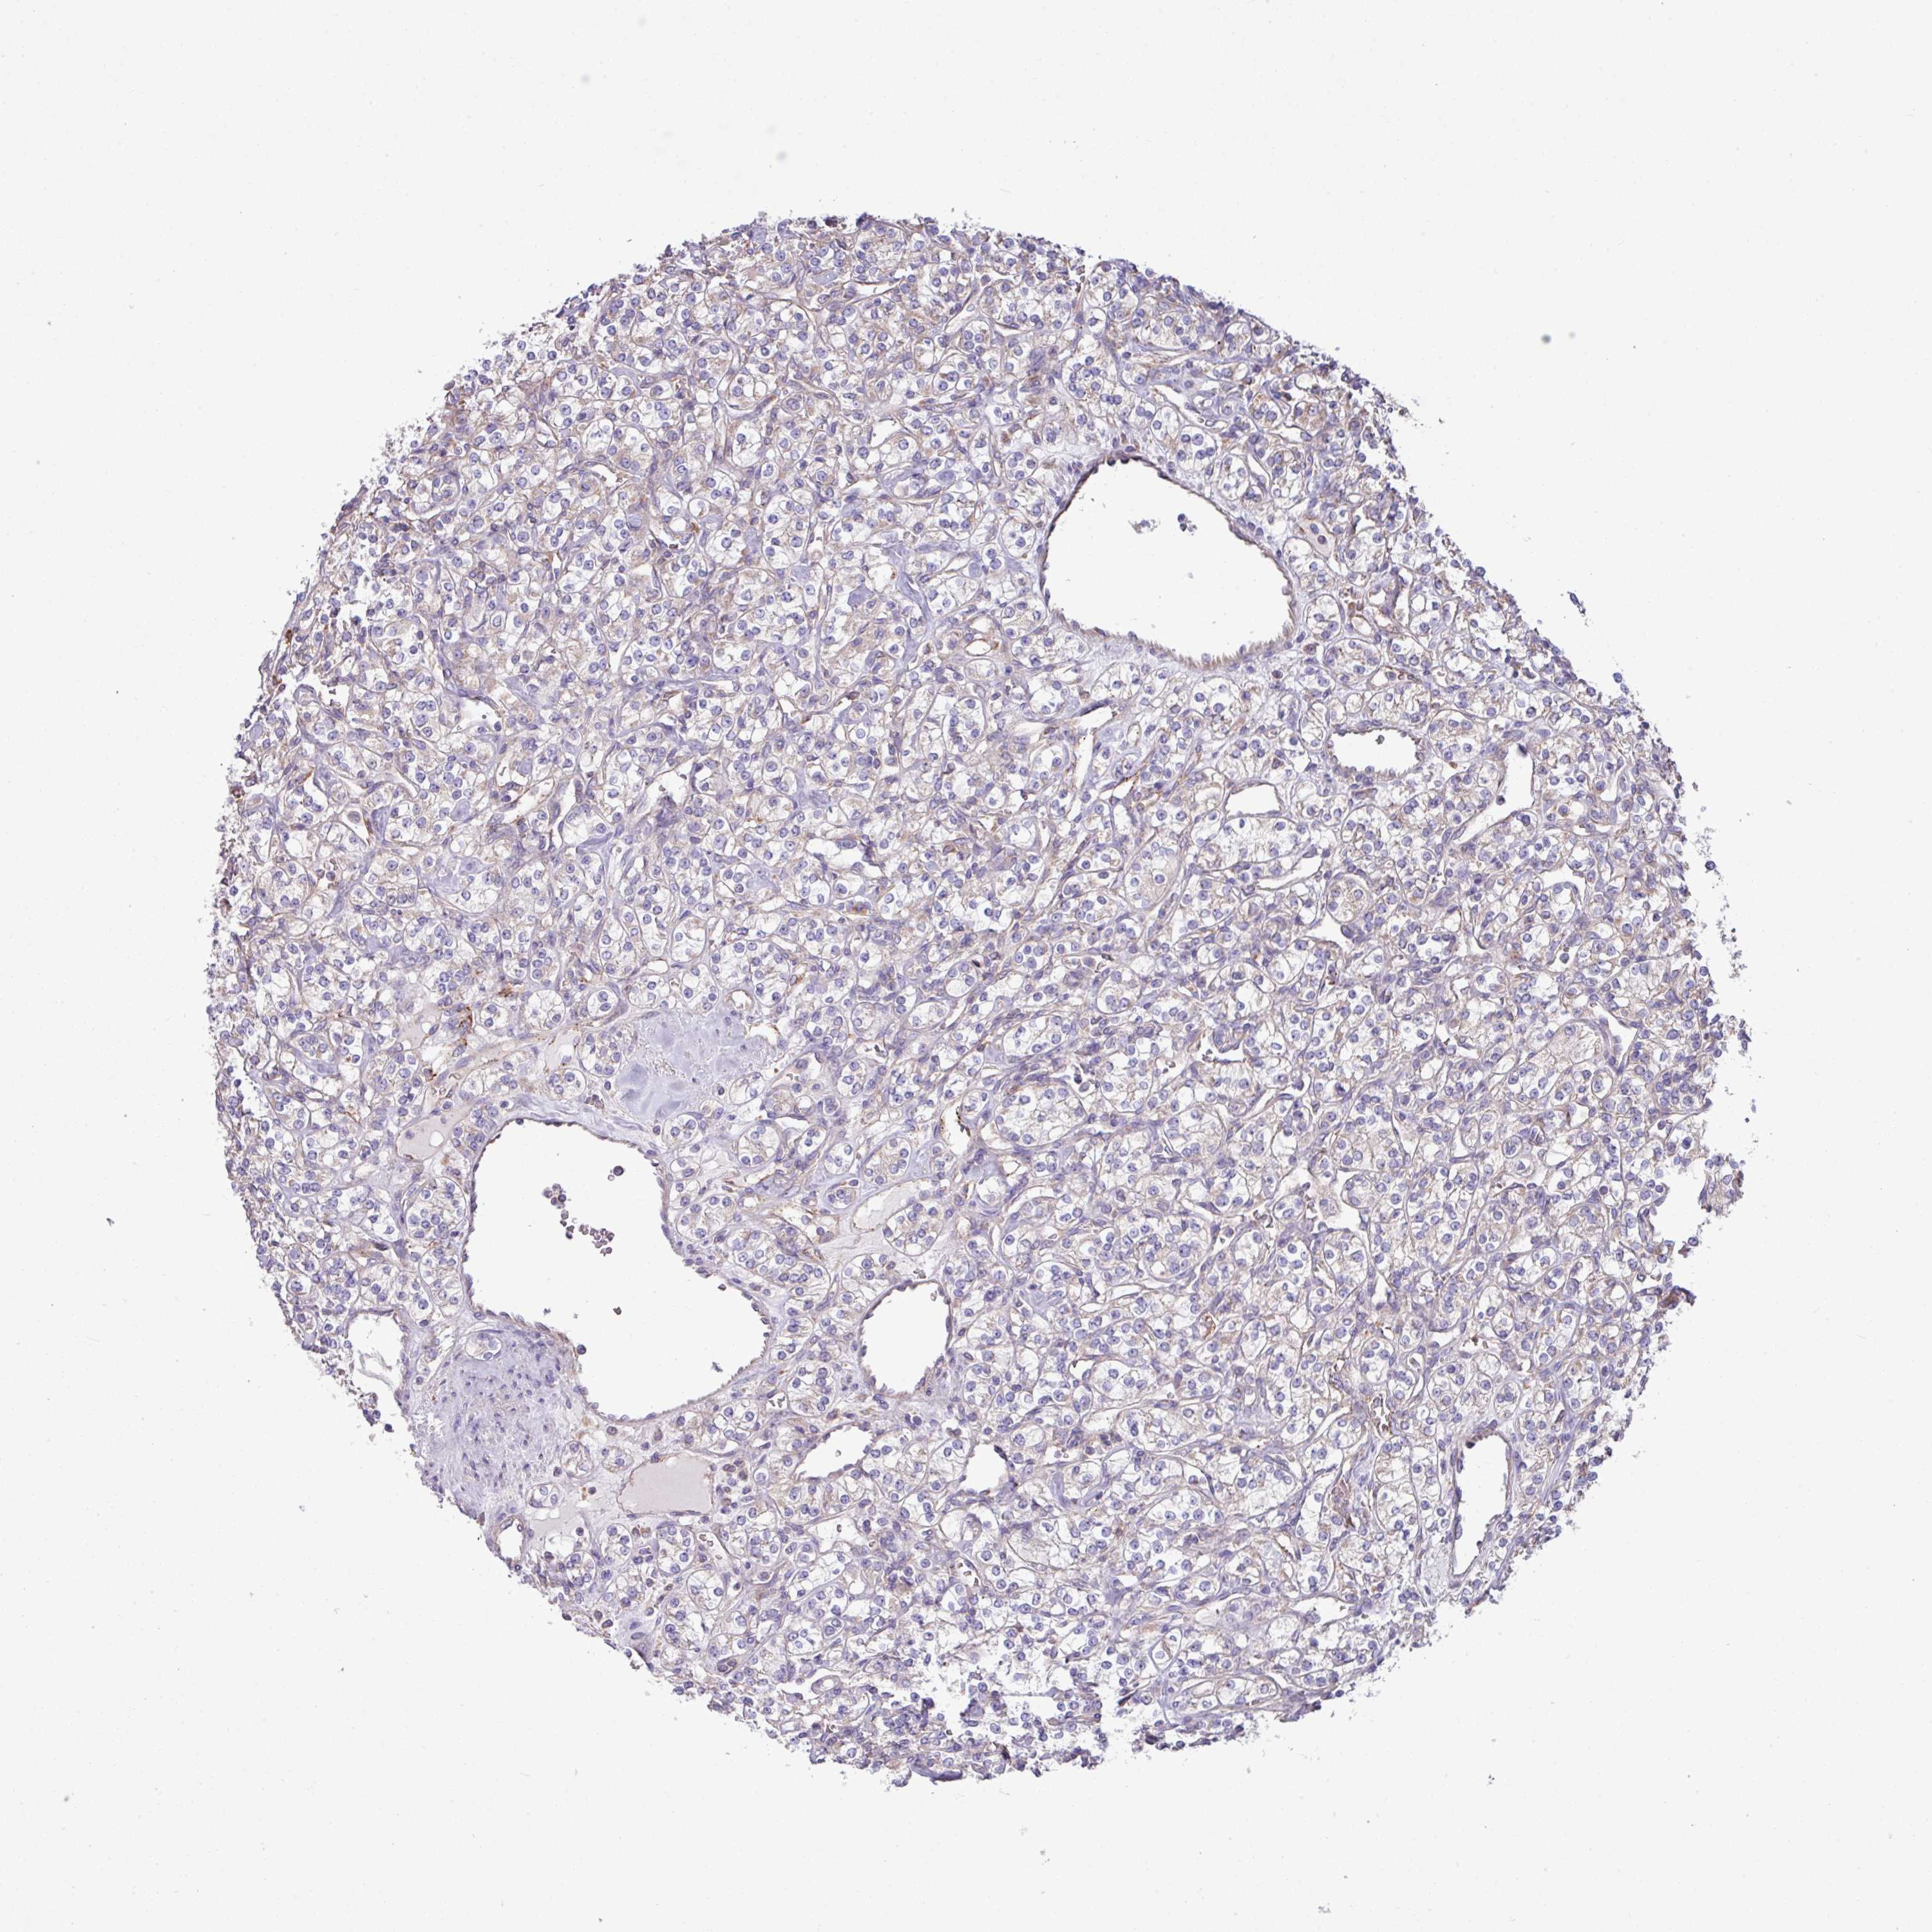

KIDNEY RENAL PAPILLARY CELL CARCINOMA (TCGA) - Interactive survival scatter ploti

The Survival Scatter plot shows the clinical status (i.e. dead or alive) for all individuals in the patient cohort, based on the same data that underlies the corresponding Kaplan-Meier plots. Patients that are alive at last time for follow-up are shown in blue and patients who have died during the study are shown in red.

The x-axis shows the expression levels (FPKM) of the investigated gene in the tumor tissue at the time of diagnosis. The y-axis shows the follow-up time after diagnosis (years). Both axes are complimented with kernel density curves demonstrating the data density over the axes. The top density plot shows the expression levels (FPKM) distribution among dead (red) and alive patients (blue). The right density plot shows the data density of the survived years of dead patients with high and low expression levels respectively, stratified using the cutoff indicated by the vertical dashed line through the Survival Scatter plot. This cutoff is automatically defined based on the FPKM cutoff that minimizes the p-score. The cutoff can be changed by dragging the vertical line or by entering a cutoff value in the square labeled "Current cut-off".

Under the Survival Scatter plot the p-score landscape (black curve; left axis) is shown together with dead median separation (red curve; right axis). Dead median separation is the difference in median mRNA expression between patients who have died with high and low expression, respectively. It is calculated as follows: median FPKM expression of dead patients with high expression - median FPKM expression of dead patients with low expression. This is intended to aid the user in visually exploring custom cutoffs and the associated p-scores and dead median separation.

Individual patient data is displayed and can be filtered by clicking on one or more of the category buttons on the top of the page. Categories describing expression level and patient information include: high, low, alive, dead, female, male and tumor stages. The scale of the x-axis can be toggled between linear and log-scale by clicking on the "x log" button. Mouse-over function shows TCGA ID, patient information and mRNA expression (FPKM) for each patient.

& Survival analysisi

Kaplan-Meier plots summarize results from analysis of correlation between mRNA expression level and patient survival. Patients were divided based on level of expression into one of the two groups "low" (under cut off) or "high" (over cut off). X-axis shows time for survival (years) and y-axis shows the probability of survival, where 1.0 corresponds to 100 percent.

PPM1J is not prognostic in Kidney Renal Papillary Cell Carcinoma (TCGA)